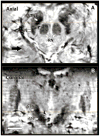

Methods: Using a 7-T MRI scanner combined with an array of acquisition schemes using multiple image contrasts, we obtained high-resolution images of human deep nuclei in healthy subjects.

Results: Superior image resolution and contrast obtained at 7 T in vivo using susceptibility-weighted imaging dramatically improved anatomic delineation of DBS targets and allowed the identification of internal architecture within these targets. A patient-specific, 3-dimensional model of each target area was generated on the basis of the acquired images.